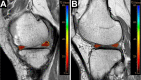

Methods: Included were 36 knees that underwent OWHTO from March 2014 to February 2016 and had postoperative serial MRI. The MRI was performed at 19.9 ± 7.4 and 52.3 ± 8.3 months postoperatively, and the cartilage and meniscal changes were evaluated by highlighting the regions of interest. We evaluated the T2 relaxation times of each cartilage and meniscal area, the cross-sectional area of the menisci, and the extrusion of the medial meniscus (MM). The meniscochondral unit was assessed using subgroup analyses according to the status of the MM.

Results: Significant decreases were seen in T2 relaxation times in the medial femoral condyle (MFC) (P < .001) and medial tibial plateau (MTP) (P = .050), and significant increases were seen in the lateral femoral condyle (LFC) (P = .036). The change was more prominent in the MFC compared with the MTP and LFC (P = .003). No significant changes were observed in the lateral tibial plateau, patella, or trochlear groove. The area of the lateral meniscus (body and posterior horn) was decreased compared with preoperative MRI (P < .001 for both). The extent of MM extrusion decreased between the preoperative, first follow-up, and second follow-up MRIs (P < .001).